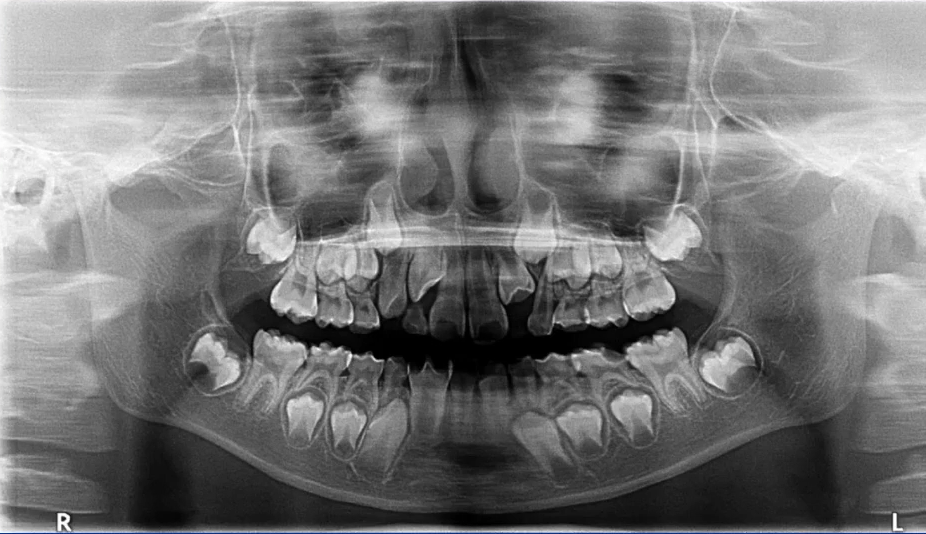

2. 混合牙列期:乳牙情况、恒牙胚观察

曲面断层片拍摄时体位相对比较简单,小患者的配合程度相对高一些。

上颌前牙区、下颌前牙区牙位辨认

患者处于混合牙列期,可以看到右侧前牙区有多生牙,下颌有融合牙的存在。